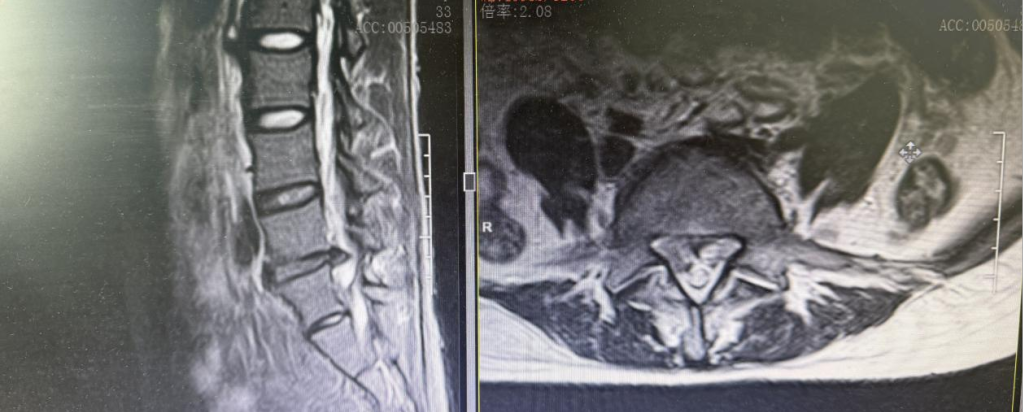

术前MRI

去年年初,付女士因长期伏案工作突发腰背剧痛,右下肢如过电般放射痛伴麻木,她在多家医院尝试过针灸、推拿、口服药物等治疗方法,但疼痛却愈演愈烈,甚至连走路都困难。最后辗转到岳阳市中医医院张氏正骨诊疗中心脊柱骨科求医。该科副主任易生辉经过细致检查,结合全面评估分析,发现付女士的椎间盘突出十分严重,已严重压迫神经根,保守治疗难以奏效,建议尽快手术治疗。为帮助付女士消除对“手术”的恐惧,易主任耐心地解释说:“此手术非传统开放性手术,是一种‘脊柱内镜微创技术’,就像‘用钥匙孔修钟表’一样精准解决问题。创伤小、恢复快。”

术后三个月复查MRI

经过充分的术前准备,付女士右侧腰5/骶1椎间孔镜微创手术十分顺利地完成。易生辉主任带领团队通过不足1厘米的切口,将突出的髓核、压迫神经的增生组织精准摘除,受压迫的神经根瞬间“松绑”。全程出血不到10毫升。术后当天付女士右下肢麻木感便消失,随即在医护人员的指导下就能下床活动。一周后满意出院。